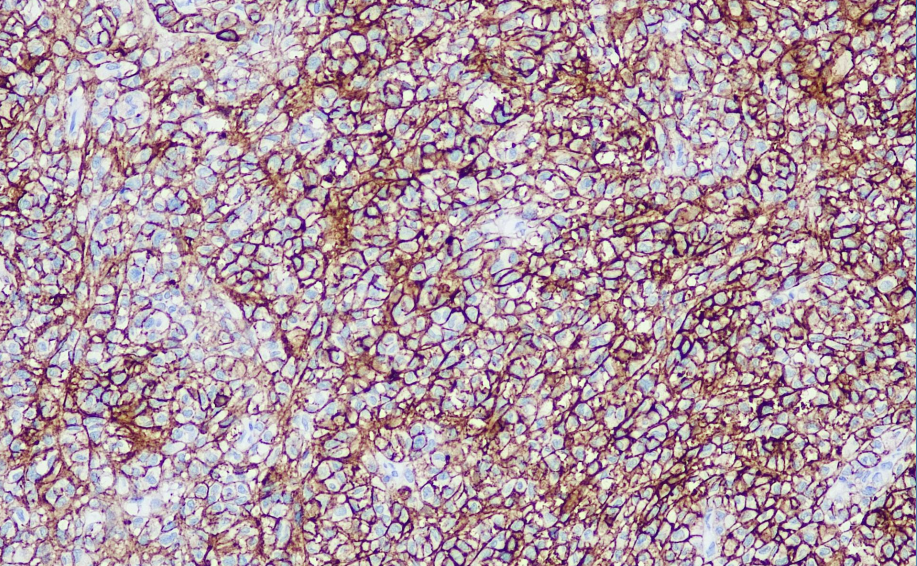

Cellular localization: cell membrane

Positive control: Malignant melanoma

The melanoma-associated antigen KBA.62 has a sensitivity similar to that of S-100p, but it has high specificity for fibroblastoid, spindle cell melanoma and sentinel microlymph node metastasis.

Melanoma Associated Antigen antibody reagents can specifically bind to Melanoma Associated Antigen antigens. The immunohistochemical kit containing Melanoma Associated Antigen antibody reagent is suitable for the precise diagnosis of melanoma.